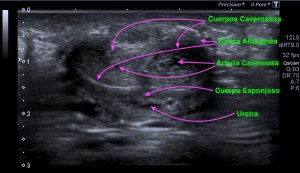

333.Revisión patología testicular. El Varicocele. Tipos y Clasificación.

Son venas del plexo pampiforme de aspecto tortuoso y dilatadas por encima de los 2 mm.

El Varicocele es primario o idiopático debido a una alteración de la vena espermática y su drenaje por mal funcionamiento de las válvulas testiculares.

Es más frecuente que el secundario debido a que la vena testicular izquierda es más larga que la derecha cuyo trazo es más corto y hace drenaje directo en la VCI.

El Varicolece Secundario se debe a aumento de presión por figuras patológicas como hidronefrosis, cirrosis o compresiones de la vena renal izquierda o neoplasias.

Varicolece. Maniobra de Valsalva.

Medida superior a 2 mm. Grado 1.

Clasificación basado en el diámetro venoso del plexo pampiniforme (en reposo):

Grado 1: Entre 2,5 y 4 mm

Grado 2: Entre 4 y 5 mm

Grado 3: Mas de 5 mm

Estas medidas son de una de las clasificaciones que se usan para el estudio del varicocele. Hay alguna otra de la que hablaremos más adelante, pero esta me parece sencilla para comprender esta habitual figura patológica.

Estas medidas son en reposo y aumentan con la maniobra de valsalva. Ojo.

Existe aumento de flujo con la maniobra de Valsalva como puedes ver en el vídeo.